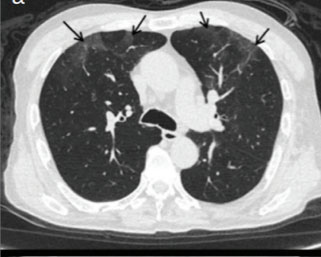

Laboratuvarda WBC 1600/mm3 (%70 PMNL, %28 lenfosit, %2 eozinofil), Hb 12.9 gr/dl, trombosit 111 000/mm3 tespit edilmiş olup, akciğer grafisi normal olarak değerlendirildi. Thoraks bilgisayarlı tomografisinde (BT) özellikle sol üst akciğer lobunda lineer sentrilobüler nodüller, buzlu cam görünümü, opasiteler saptandı (Resim 2).

Resim 2. Yüksek çözünürlüklü akciğer tomografisi